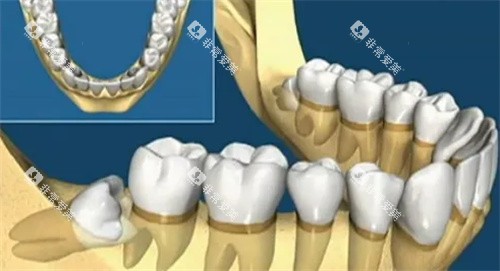

一走进医院,就能看到各种新型的口腔医疗设备,像CBCT机、全景机、激光设备啥的,这些可都是给诊疗效率和精细度加分的“神器”。

这家医院能做的口腔项目可不少,补牙、儿童牙科、牙齿美白、烤瓷牙、口腔修复、口腔预防保健、洗牙等等,统统都能搞定。